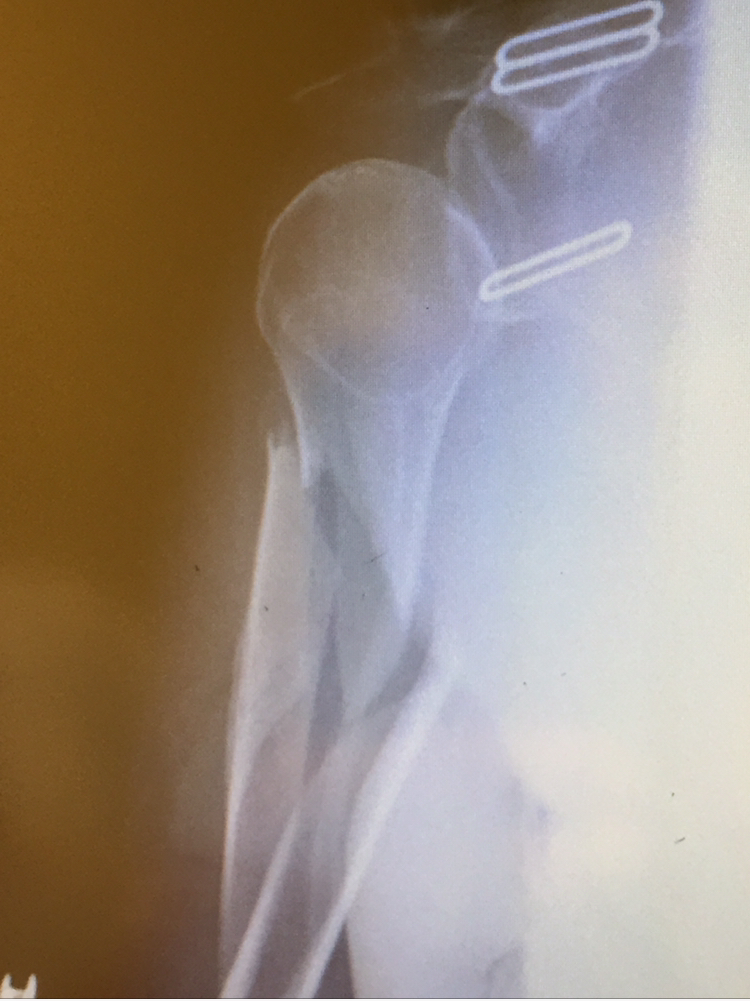

Arm and Elbow Fractures

When Ginny broke her arm in May we were worried that it would put a dampener on her summer fun. After a very successful surgery with Dr. Fabricant and the awesome team at HSS, Ginny kicked off the summer with a cast on that went all the way up to her shoulder. No cast could hold Ginny back though, and within a few weeks of getting it off she was already almost back to 100%.